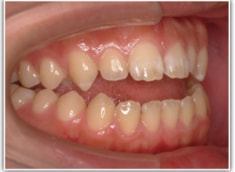

開咬(かいこう:オープンバイト)ケース

治療法:表の矯正(T21ブラケット)

(インプラントアンカーや外科矯正は行わず、エラスティックと機能訓練のみ)

治療後(2年2ヶ月後)